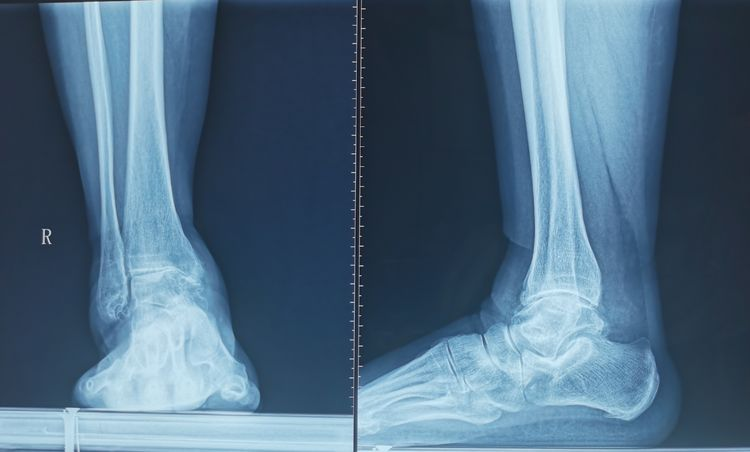

Takakura-Tanaka 3a距骨內翻,右踝關節內側間隙變窄,軟骨下骨接觸,踝關節內外側大量骨贅形成。

左踝關節退變,骨性關節炎,骨贅增生,踝關節無內外翻。

踝關節退變,內外側骨贅形成,軟骨破壞,關節間隙變窄。